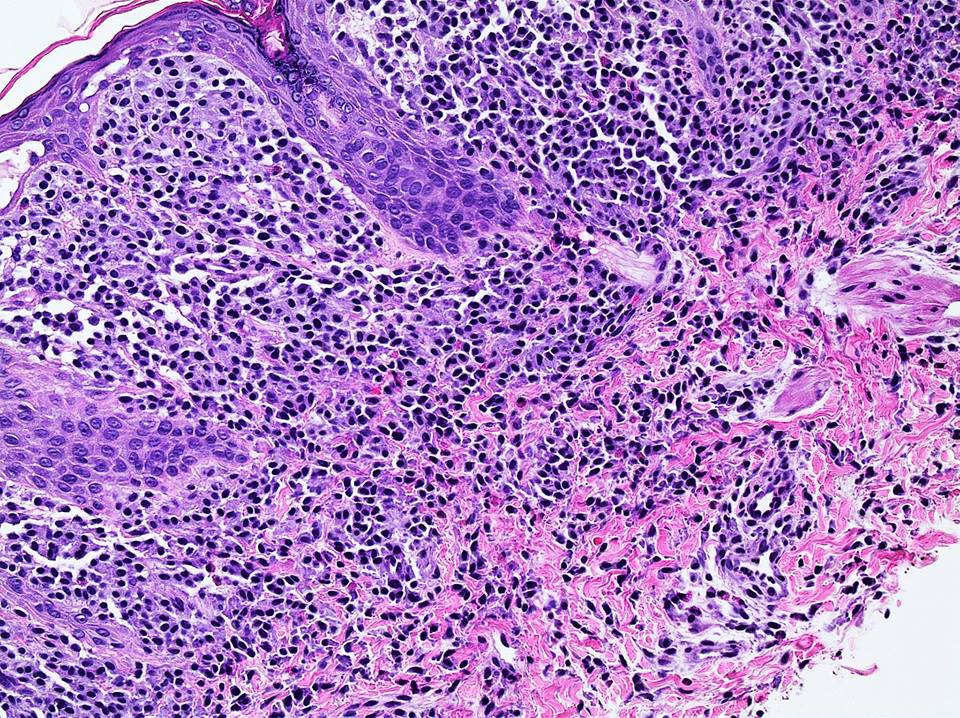

Microscopic (histologic) description

- Within the macules and plaque, mast cells are predominantly in papillary dermis

- Mast cells are round or spindle shaped with abundant eosinophilic cytoplasm, distinct cytoplasmic boundaries, large pale nuclei

- Eosinophils are often present

Microscopic (histologic) images